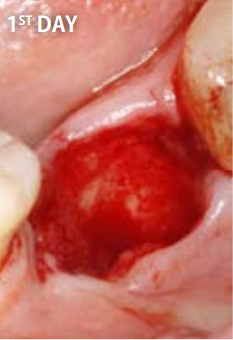

上記の写真はリッジプリザベーションにPRGFを用いたもので、非常に高い効果を得ることができます。

●PRGFを利用した場合

抜歯直後

抜歯してできた穴にPRGFを入れると、上皮や骨の再生が促進され、短期間で抜歯窩がふさがります。また、抜歯後の痛みと腫れも軽減します。